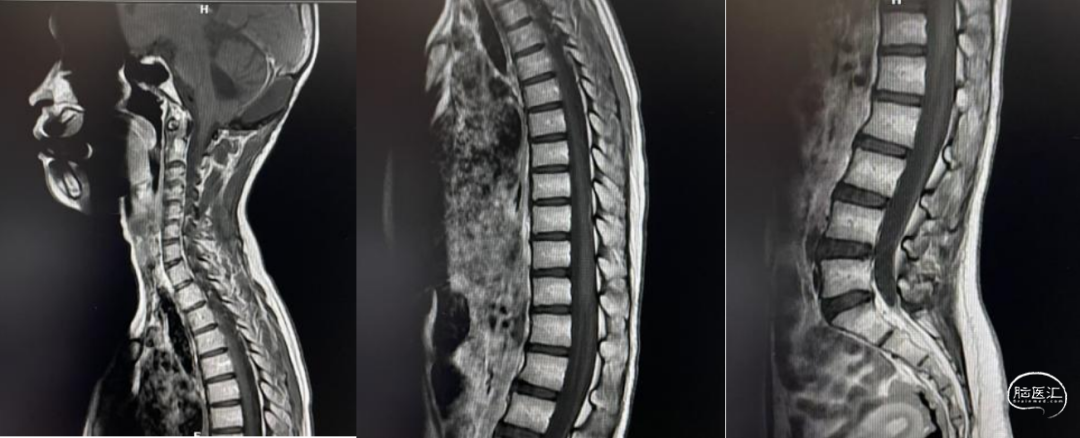

头部MRI显示:小脑蚓部可见一团块样等T1、等-长T2信号灶,边缘模糊,大小约3.5*3.6cm,增强后病灶明显强化,第四脑室明显受压,慕上脑室轻度扩张,中线结构居中。

病理检查:髓母细胞瘤。免疫组化:CgA(+),EMA(-),GFAP(-),Ki67(60%),NSE(+),Syn(+),Vimentin(+)。

经枕下后正中入路全切除肿瘤。

术后按期进入后续放射治疗与化疗并顺利完成。

患儿术后存在骨瓣下积液,皮下穿刺抽吸未能消除。排除感染后未予进一步处理。后续复查未见消失。